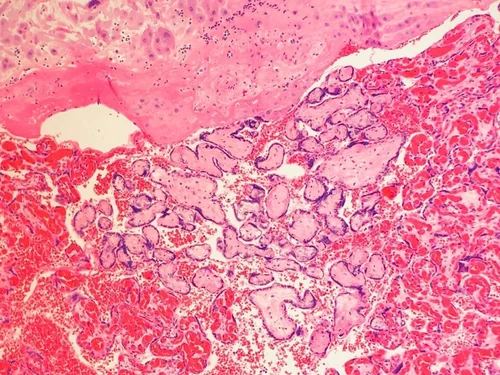

Acute subchorionitis

Acute chorionitis - neutrophils within cellular chorion

Can be associated with placental abruption, umbilical cord occlusion, or difficult manual extraction